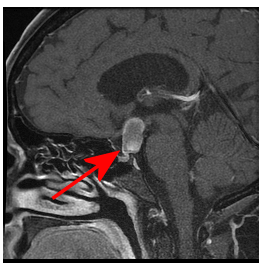

Figure 1A: Sagittal T1 post contast thin section through the midline demonstrates a mass separate from the pituitary (yellow arrow), centered in the suprasellar cistern (red circle).

Figure 1B-D: The mass is very T2 hyperintense (B) with a dependent nodule of lower T2 hyperinstensity (blue arrow). Coronal T1 post contrast (C) and pre contrast (D) demonstrate subtle nodular enhancement along the inferolateral margin of the mass (green arrow).